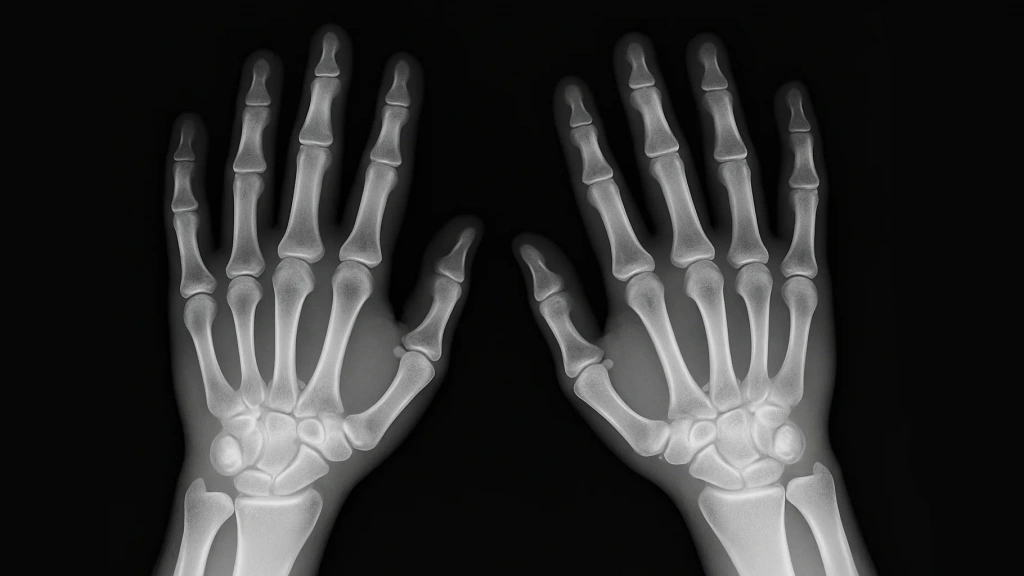

Диагностика включает в себя визуальный осмотр, оценку подвижности сустава, выявление (при наличии) отека, деформаций и болевых точек. Инструментальные методы — рентген, УЗИ и МРТ — помогают выявить костные повреждения, сужение суставной щели, оценить состояние мягких тканей и более детально рассмотреть состояние хрящей, нервов и мелких структур. При туннельных синдромах проводят ЭНМГ (электронейромиографию) для оценки проводимости нервов.